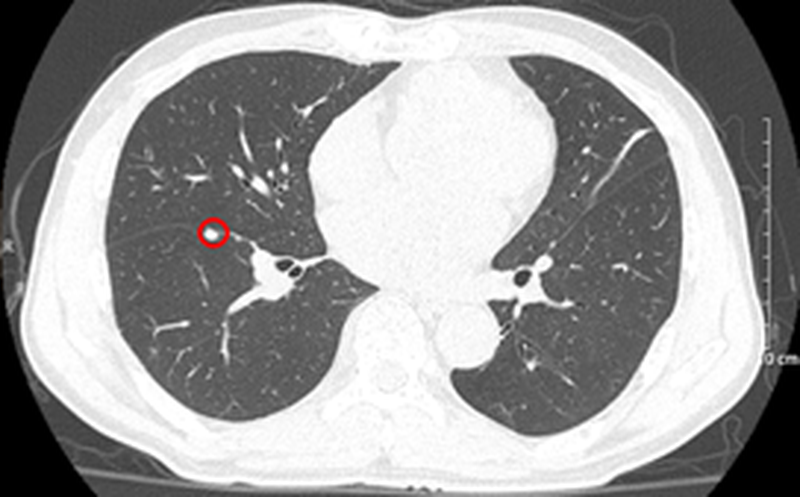

Bệnh nhân khám tại Khoa Khám bệnh, Bệnh viện Bạch Mai, chụp cắt lớp vi tính lồng ngực phát hiện khối, nốt ở nhu mô phổi và khối nhu mô gan. Bệnh nhân sau đó được chuyển đến Trung tâm Y học hạt nhân và Ung bướu.

Nhu mô hạ phân thùy VII có vài khối, nốt kích thước lớn nhất 33x26mm giảm tỷ trọng trước tiêm, ngấm thuốc thì động mạch (vòng tròn đỏ), thải thuốc thì tĩnh mạch cửa (vòng tròn).

Căn cứ vào các kết quả cận lâm sàng, xét nghiệm… bệnh nhân được chẩn đoán xác định ung thư phổi trái không tế bào nhỏ di căn phổi EGFR (+), giai đoạn IV cT3N0M1 – Ung thư đường mật type ống nhỏ di căn hạch rốn gan, giai đoạn IIIB cT2N1M0/viêm gan B.